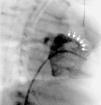

Case 1A 2-year-old asymptomatic boy with a heart murmur underwent an echocardiogram which showed turbulent flow in the subaortic region. He was catheterized and the aortic angiogram revealed a hemodynamically insignificant fistulous tract between the right sinus of Valsalva and the RV (Figure 1).